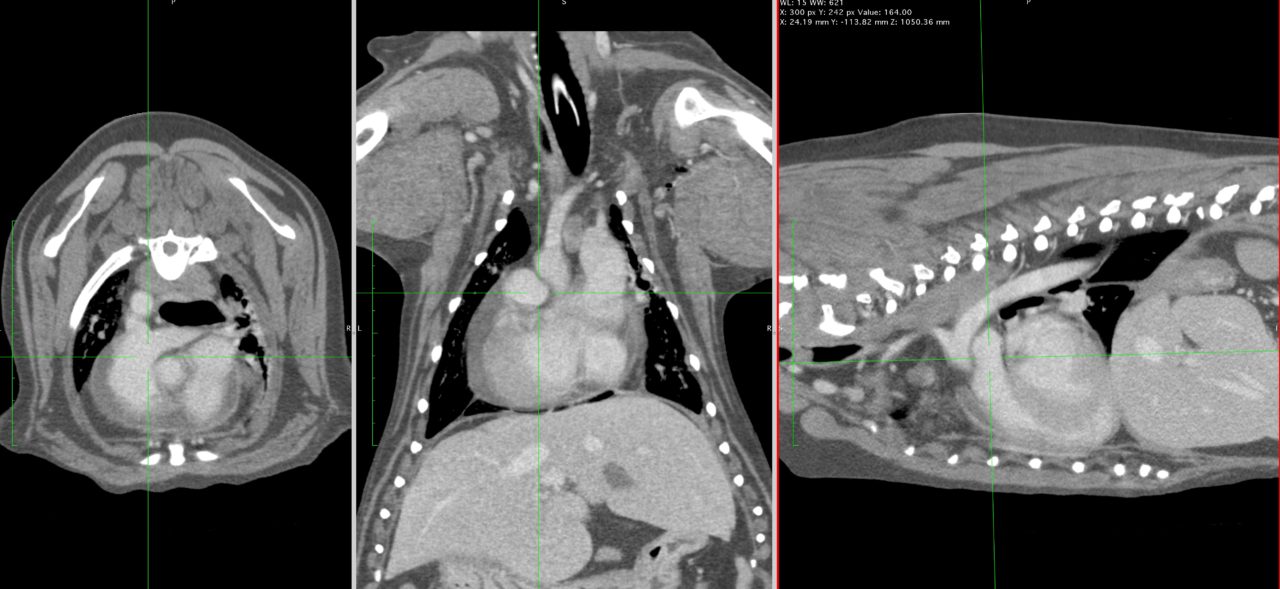

9歳の柴犬が散歩中に突然倒れる事があるとのことでかかりつけを受診しました。幼少時よりてんかん発作を発症する事があるが、今回の様子はてんかんの時とは異なる様だとのことで精査を希望され来院しました。心音は微弱でマッフルを呈していました。また、腹水の貯留も確認されました。心臓超音波検査では心膜液の貯留が確認されました。心嚢水の除去を行なったところ、出血性の心嚢水でした。数日間は心嚢水の除去のみで一般状態は改善していました。しかし、再発すると虚脱するといった症状が確認されたため、再発性の心タンポナーゼを回避するために、胸腔鏡下で心膜切除術を実施しました。同時に中皮腫、血管肉腫、特発性との鑑別にCTによる精査も実施しております。心膜の病理検査では腫瘍性の変化はなく、著しく繊維化した心膜であり、特発性と診断されました。胸腔鏡下での手術であったため、数日間の入院で痛みも少なく良好に経過しています。